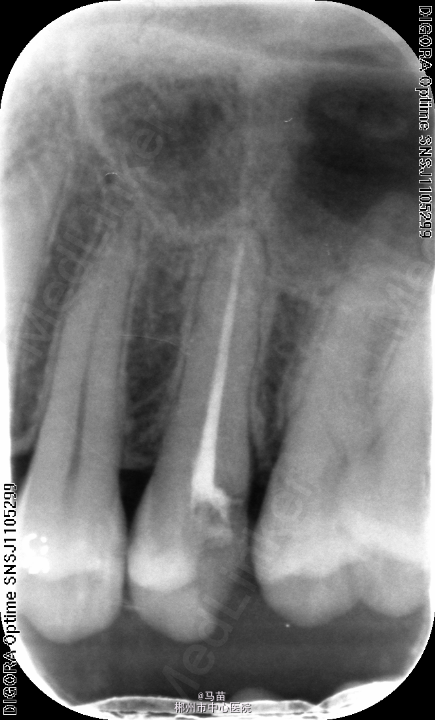

左上5慢性牙髓炎,处理,去腐未尽穿髓,局麻下,开髓揭顶,根管预备第一次测长度17CM,插入牙胶拍片,欠长约3mm,重新清理根尖段牙髓,测长度21CM,完成根管预备及充填

根管预备中,测得长度与估计不符,不能盲目继续根备,最好拍诊断片